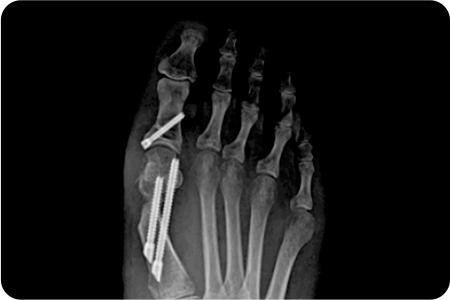

과거에는 튀어나온 뼈만 깎는 수술을 해서 통증도 심하고 재발하는 경우도 많았지만

최근에는 엄지발가락과 인대를 일자로 잡아 주는 절골술을 시행하여 재발률을 크게 낮췄습니다.

엄지발가락 부위에 약 2~3mm 크기의 작은

구멍을 만들고 특수한 미세 절삭 기구를 사용해

변형된 뼈를 절골하여 올바르게 교정합니다.

최소침습 무지외반증 수술은 발가락 뼈를 작은 절개로 교정하여,

의사가 직접 특수 장비를 통해 변형된 뼈를 정밀하게 절골하고 올바른 정렬로 맞추는 방식으로 진행

됩니다.